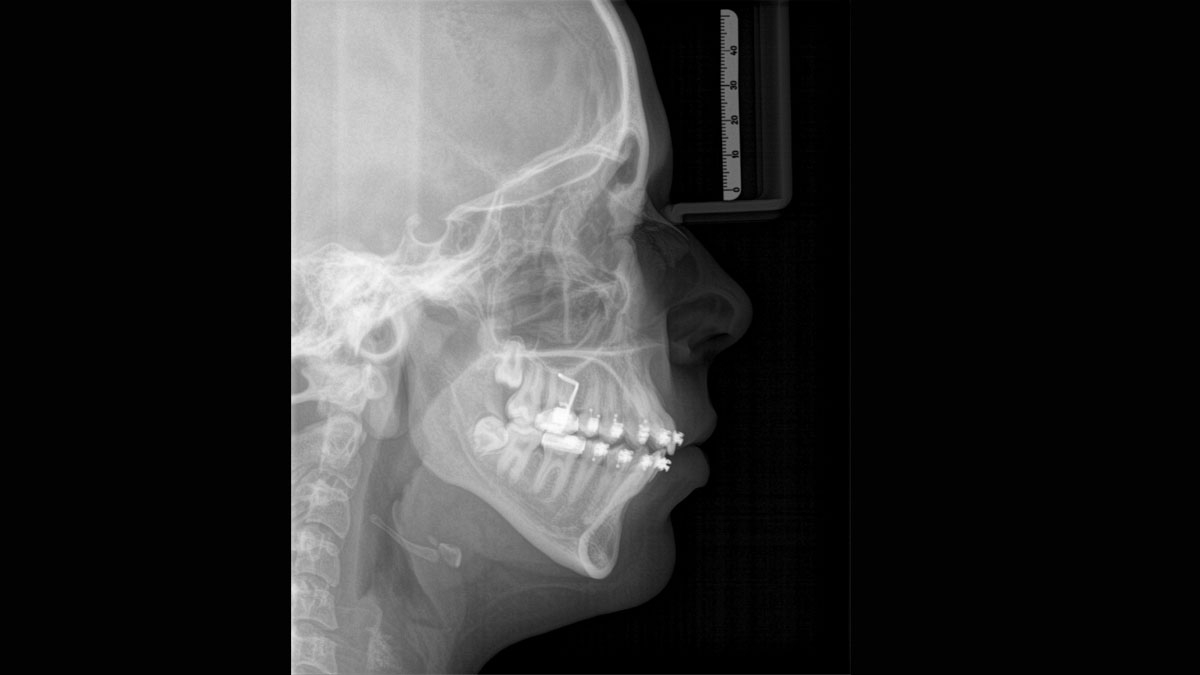

We developed a 10-point concept for easy patient positioning and X-ray imaging. Our concept is primarily about two things: high image quality and comfort for the patient and the assistant. This concept supports and provides the tools needed to ensure high-quality images for treatment analysis and focuses on ergonomics and comfort for the patient and assistant. The patented bite block technology, for example, automatically establishes the correct inclination of the patient's head, positioning the patient in the occlusal plane, partnering with the 3 point head fixation and firm handles to ensure stable positioning-limiting unnecessary correction scans.